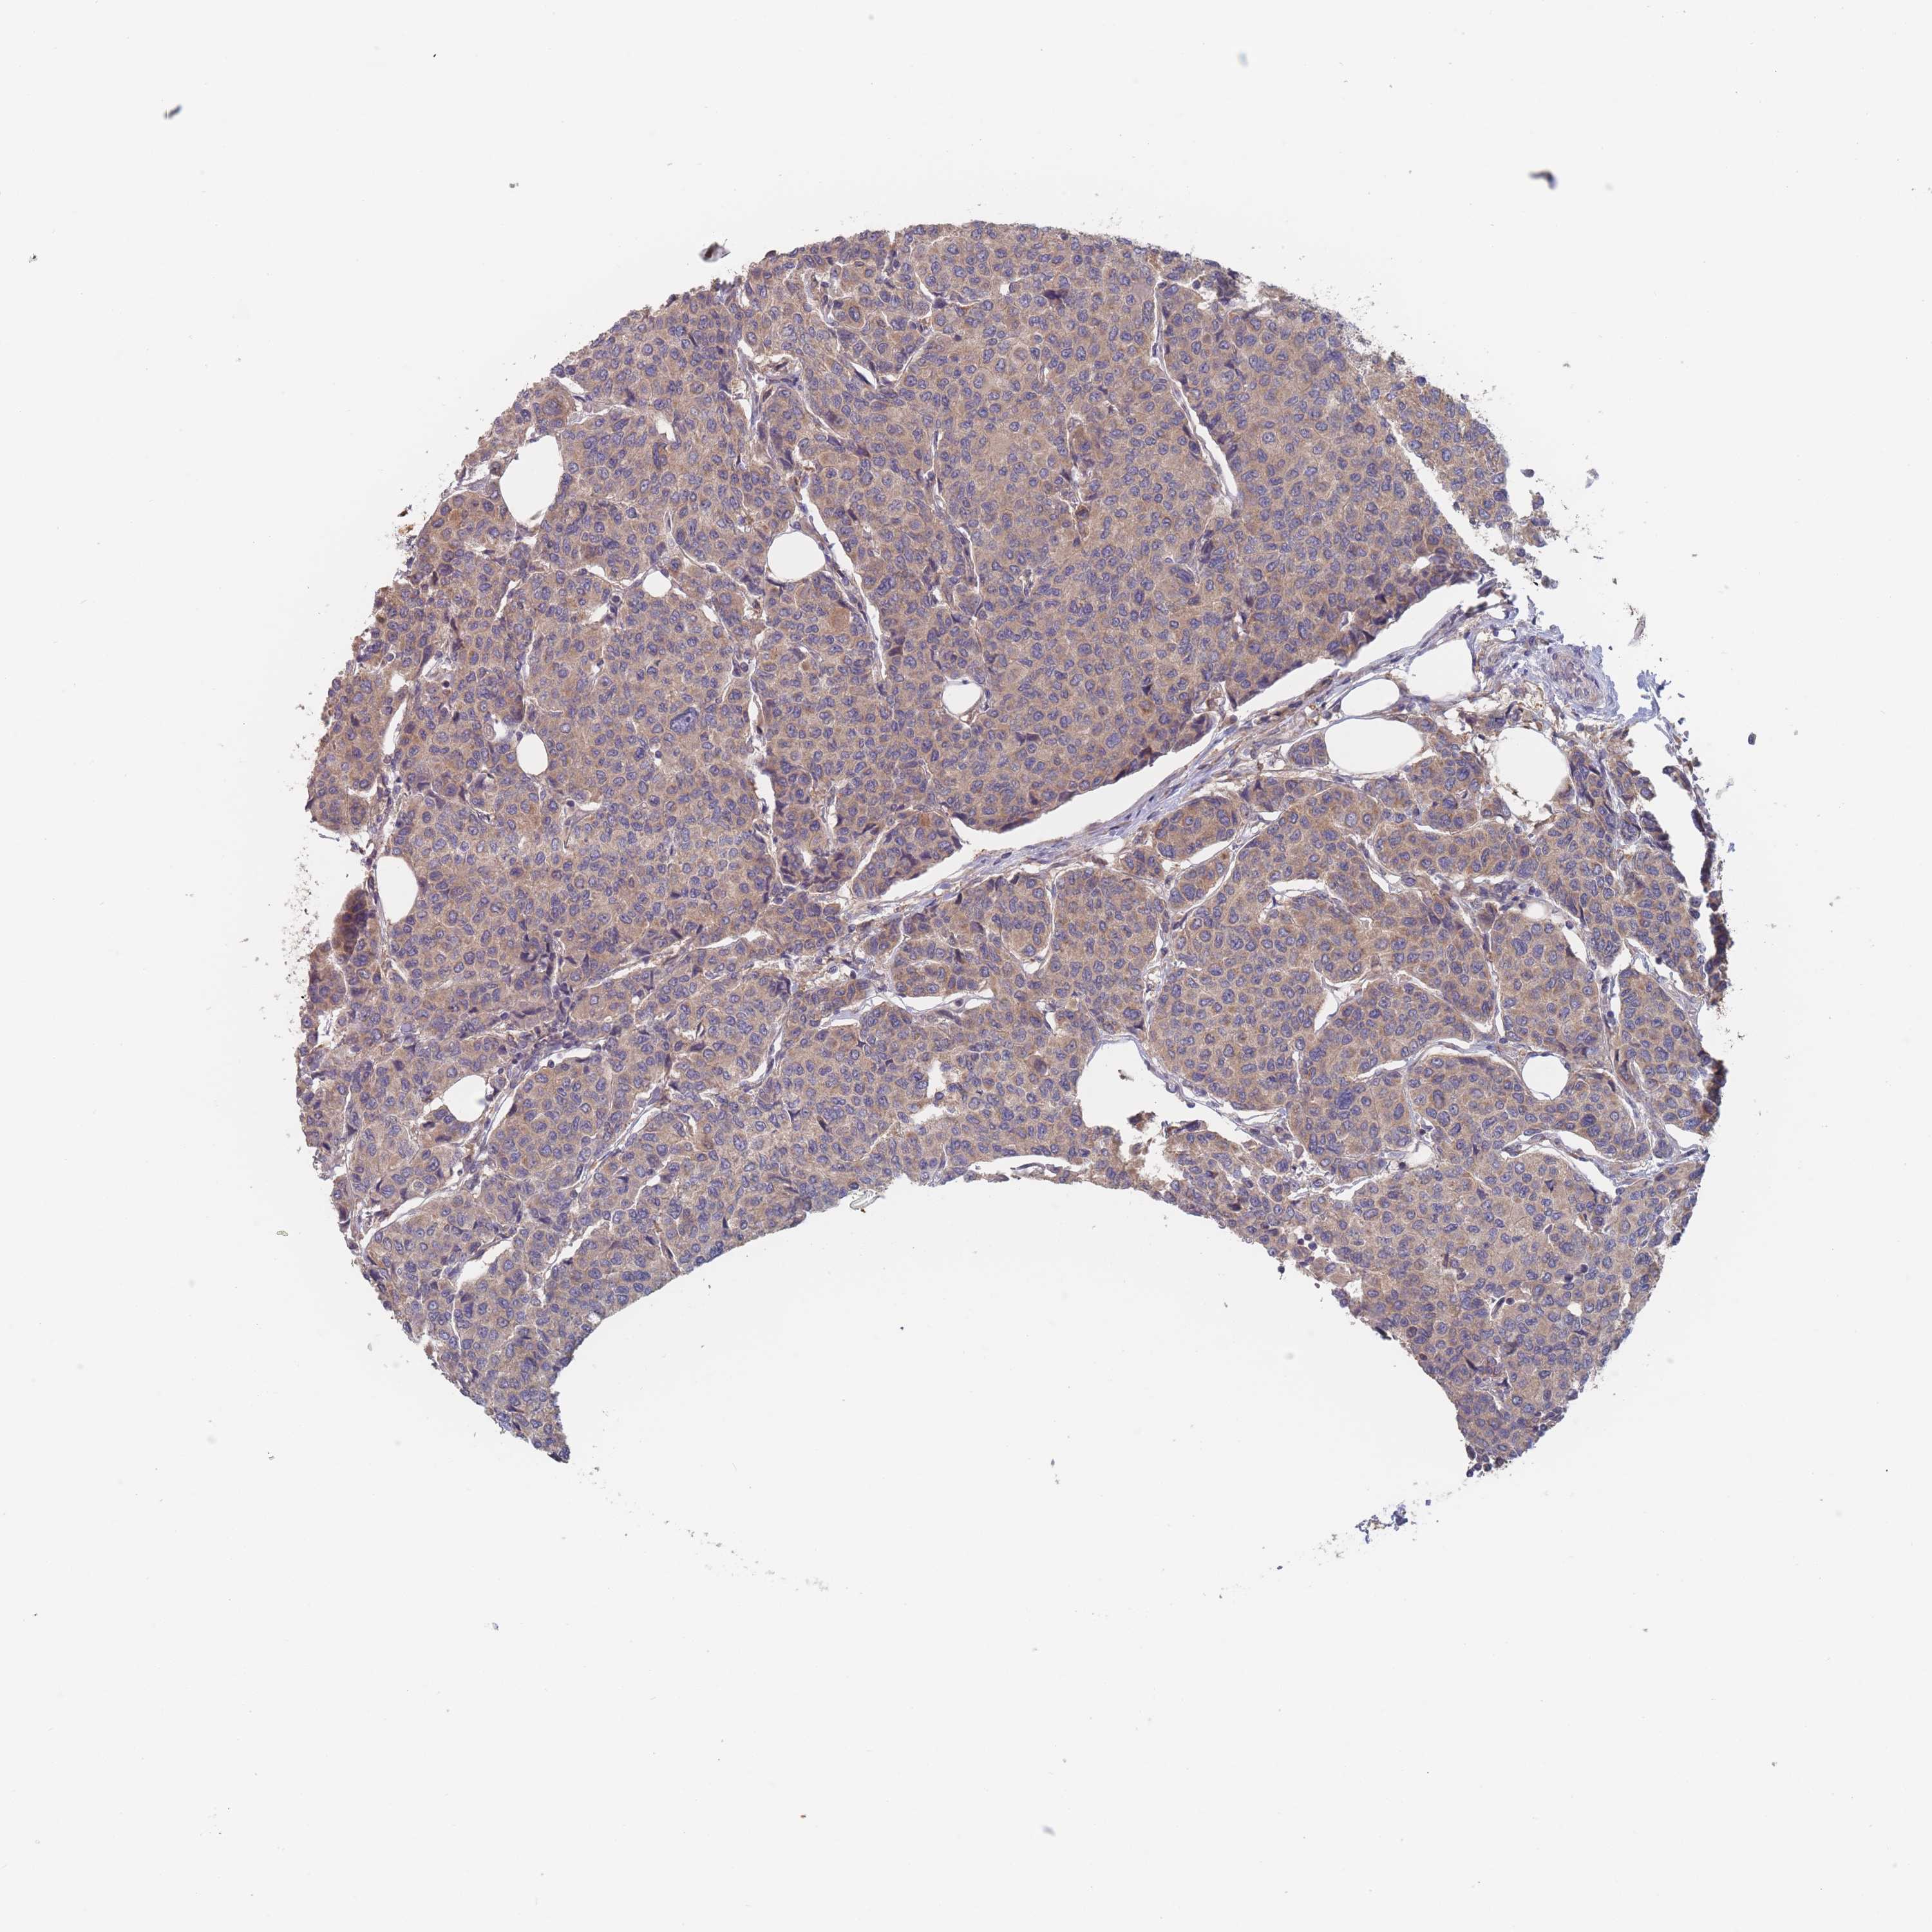

BRCA TCGA BRCA VALIDATION PROTEIN EXPRESSION